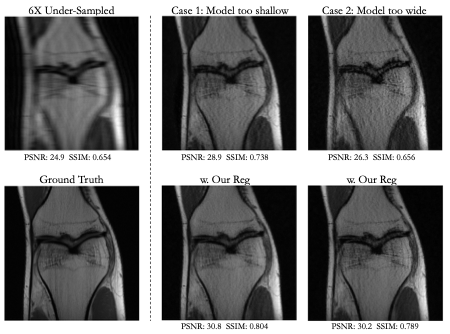

Visual and numerical results for the multi-coil knee and brain datasets under 4x and 6x acceleration are shown in Figs. 2-5 and Tab. 1. We tested U-Net architectures with typical widths (128 vs. 256 channels) and depths (3 levels vs. 5 levels). Additional results for total-variation (TV) regularized DIP [7] are shown in Tab 1. Figs. 2-5 indicate that suboptimal architectures lead to severe artifacts in the reconstructed images (top rows). Utilizing our regularization strategy, we observe appreciable improvements in image quality over the baselines, especially for 4x acceleration. Notably, the extent of improvement is similar regardless of the architecture. This suggests that controlling the frequency biases of the network architecture via proper regularization might be as effective as modifying the architecture in DIP based reconstruction. In contrast, TV regularization does not exhibit comparable performance. Our strategy works consistently on MR images acquired from different organs (i.e., knee and brain).

Fig 3. Results for a 6x under-sampled multi-coil knee scan. Our regularization strategy improves reconstruction over architectures that are too shallow (3-level UNet) or too wide (256 channels/layer).

Fig 4. Results for a 4x under-sampled multi-coil brain scan. Our regularization strategy improves reconstruction over architectures that are too shallow (3-level UNet) or too wide (256 channels/layer).